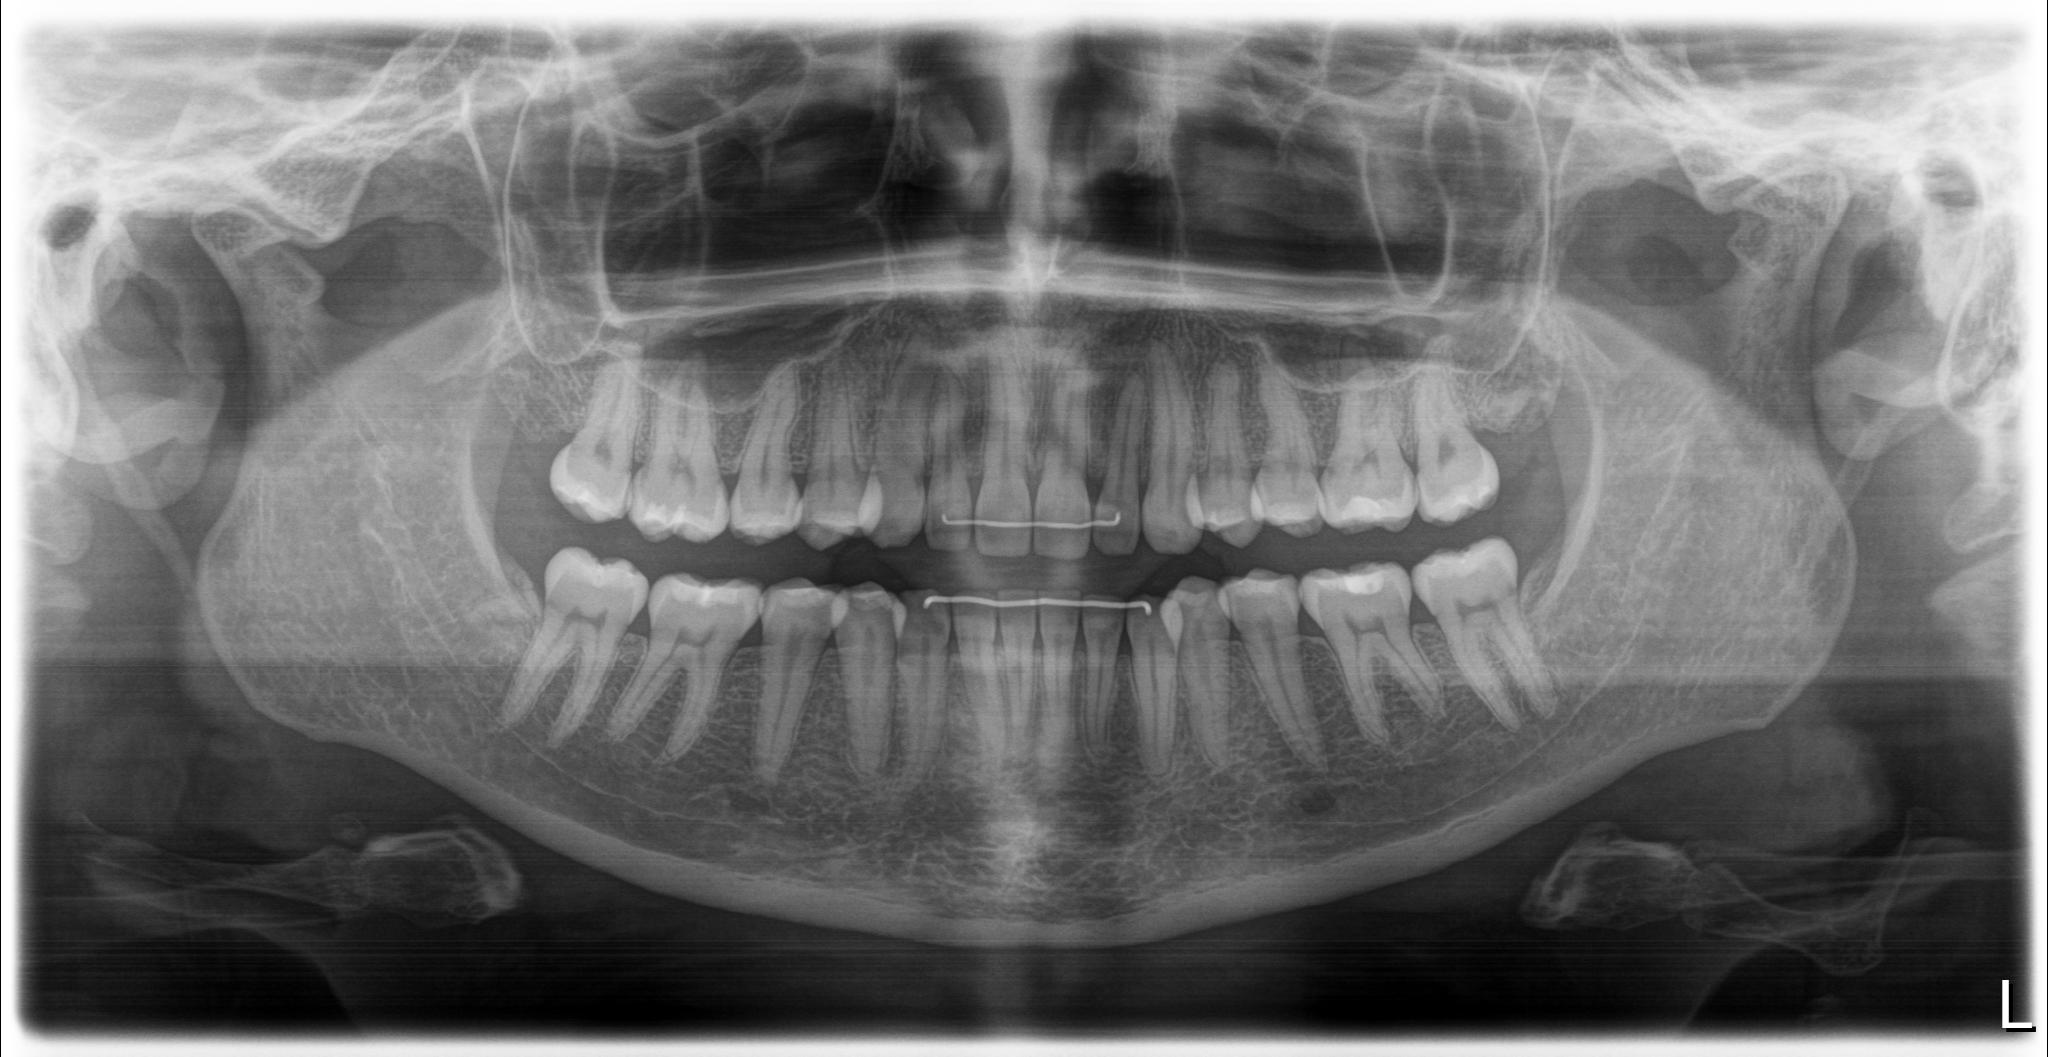

thanks @TML ! sorry to hear you are going through similar symptoms too! Heres my panoramic x-ray and CT scans that the chiropractor took. I havent got the CT imaging taken by the head and neck surgeon but hopefully they would be able to send this to me also. I saw my rheumatologist today who ordered a neck MRI/A of the vascular structures -I am unsure whether this is the correct imaging though to check for vascular compression?

@goldenretriever see attached your imaging. Both of your styloids appear elongated. One appears to be one long piece, while on the other side you have a gap where the styloid looks like a normal length but then a cm or so lower the stylohyoid ligament looks calcified.

I will say, even without contrast, I can tell your right styloid is closer to your C1 than your left styloid. Which means I suspect your right IJV and potentially vagus nerve is being compressed. Won’t know for sure without contrast though.